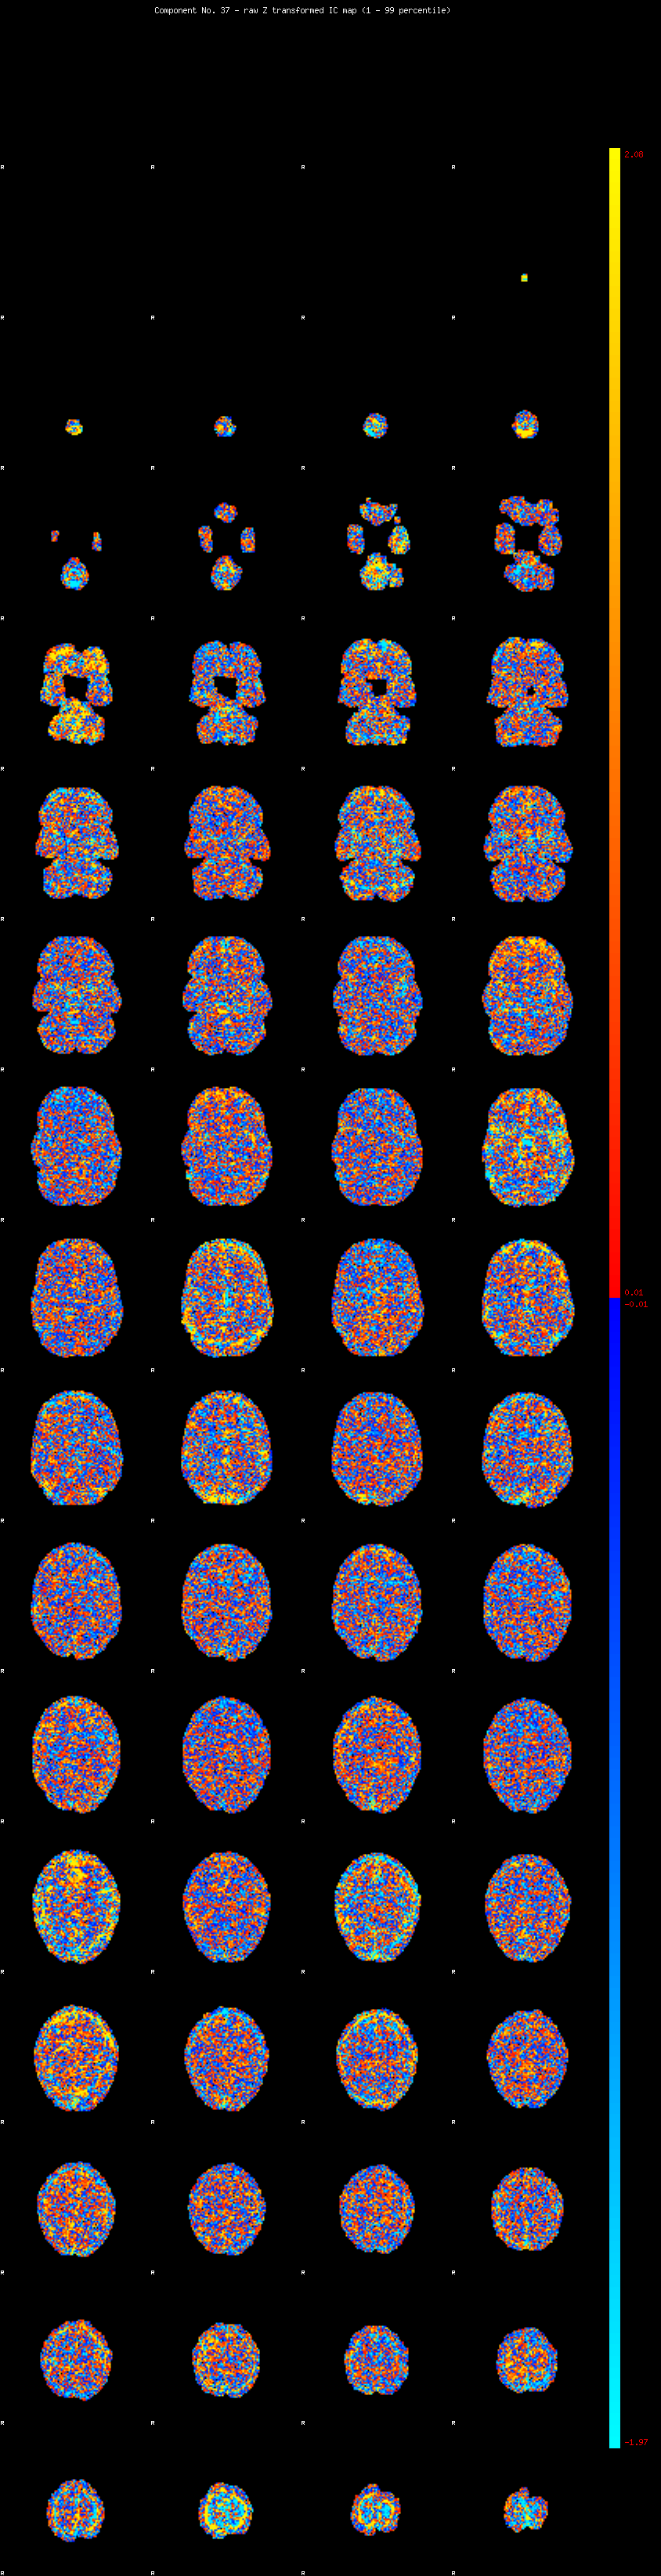

IC_37 Mixture Model fit

Means : -0.000000 2.451697 -2.267468

Vars : 1.000000 1.878576 1.354735

Prop. : 0.923431 0.042560 0.034008